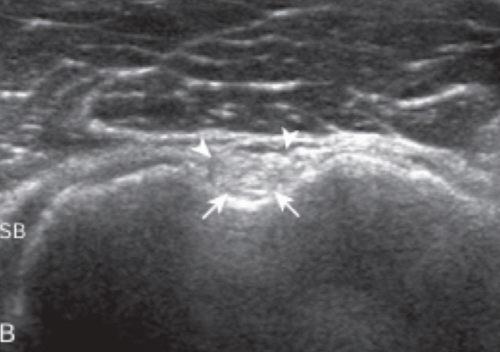

목차 반응형어깨 검사를 위하여 환자는 의자의 발이 고정된 등받이 없는 회전의자에 앉고, 검사자는 이동성이 좋은 바퀴 달린 의자에 앉는다. 환자의 왼쪽어깨를 검사할 때에는, 환자가 초음파기기를 향하여 앉고, 검사자는 초음파기기와 환자사이에 엇비슷하게 앉는다. 오른쪽 어깨를 검사할 때에는, 검사자가 기계를 향하여 앉고, 환자는 검사자를 엇비슷하게 마주 보고 앉는다. 어깨의 초음파 검사는 적어도 10 Mhz 이상의 주파수를 가진 탐촉자를 사용한다. 환자의 체격이 좋고 비대하거나, 어깨뼈오목테두리(glenoid labrum)등, 어깨 깊은 곳에 있는 구조물을 보려면 낮은 주파수의 탐촉자를 쓰기도 한다. 검사 항목을 빠뜨리지 않고 검사를 하기 위하여, 다음에서 설명하는 검사 순서에 따라 단계별로 하는 것이 중요하다. 다른 관절에서는 필요한 부분만 골라서 중점적으로 검사하기도 하지만, 어깨에서는 통증의 원인이 애매하고, 또 다른 부위의 병변에 의한 통증이 어깨에 연관통증(referred pain)을 나타낼 수 있고, 또 어깨의 질병이 다른 부위에 연관통증을 일으킬 수 있기 때문이다. 물론, 통증이나 증상이 있는 곳을 추가로 검사하는 것은 필수적이다. 자세 1. 두 갈래 근 긴 힘줄환자는 검사받는 팔의 손바닥이 위를 향하게 하여 손등을 환자의 넙다리에 놓는다. 이 자세를 중립 상태라고 한다. 탐촉자를 가로축 방향으로 어깨의 앞쪽에 놓으면 두 갈래 근 긴 힘줄(long head of biceps brachii tendon)이 두 갈래 근고랑에 놓인 것을 볼 수 있다.  두갈래근 긴힘줄 초음파 영상(short axis) 이 자세는 어깨의 앞쪽에서 중요한 표식자(landmark)인 두 갈래 근고랑의 움직임을 보면서 회전근띠를 검사하기에 좋다. 탐촉자를 피부에 대면 두갈래근 긴 힘줄이 정상인데도 검고 낮은 에코로 보인다. 이를 비등방성(anisotropy) 허상이라 한다. 그 이유는 힘줄이 아래로 갈수록 비스듬하게 기울기를 가지면서 깊어지기 때문이다. 탐촉자를 힘줄에 대해 90도가 되도록 조절하면 비등방성이 사라지고 힘줄은 높은 에코로 바뀐다. 가로축 방향에서 위, 아래로 두 갈래 근 긴 힘줄을 따라가면서 검사한 뒤에 탐촉자를 90도로 돌려서 세로축 방향에서 검사한다. 마찬가지로 입사 초음파가 힘줄에 대해 직각이 되도록 탐촉자의 각도를 조절하면서 검사한다. 세로축 방향에서 작은 거 친면은 특징적으로 세모꼴로 보이는데 그 바로 바깥쪽의 두 갈래 근고랑에는 두 갈래 근 긴 힘줄이 세로로 길게 놓여있다.  두갈래근 긴힘줄 초음파 영상(longitudinal) 자세 2. 어깨밑근과 두갈래근 긴 힘줄의 탈구자세 1 '중립자세'에서 탐촉자를 어깨 앞쪽에 가로축 방향으로 놓으면 두 갈래 근 긴 힘줄(biceps tendon)보다 안쪽으로 어깨밑 근(subscapularis)이 보이는데, 어깨밑근의 긴 축영상(long-axis images)이다. 이 자세에서 어깨밑근은 심한 비등방성 때문에 매우 검게 보인다. 환자의 팔을 바깥돌림(external rotation)하면 어깨밑근이 입사 초음파에 대해 수직으로 놓이게 되면서 비등방성이 사라지게 되고 정상적인 높은 에코로 바뀐다. 이 자세에서 탐촉자를 위, 아래로 움직여서 어깨밑근이 작은 거 친면에 넓게 붙는 것을 본다. 팔을 안-바깥돌림(internal and external rotation)하면서 두갈래근 긴 힘줄이 두 갈래 근고랑에서 벗어나지 않음을 관찰한다. 두 갈래 근 긴 힘줄의 부분이탈이나 어긋남(subluxation or dislocation)이 팔의 바깥돌림에서만 나타날 수 있다. 탐촉자를 90도 돌려 세로로 놓으면, 탐촉자는 어깨밑근의 주행방향에 대해 90도 각도로 놓이게 되고, 어깨밑근을 짧은 축영상(short-axis images)에서 검사한다. 어깨밑근의 짧은 축영상에서, 높은 에코의 힘줄다발(tendon bundle) 사이사이에 낮은 에코의 근육이 줄무늬(striation)로 보이는데 이는 정상소견이며, 공간복합기능(spatial compound function)이 없는 초음파기기에서는 대조도가 더 뚜렷하게 보인다. 자세 3. 봉우리빗장관절 및 봉우리밑-세 모근밑 윤활주머니봉우리빗장관절(acromioclavicular joint)은 탐촉자를 빗장뼈(clavicle) 먼쪽(distal)에 빗관상면(coronal-oblique plane)으로 놓고 손으로 만지면서 그 위치를 찾거나, '자세 1' 에서처럼 가로축 방향으로 놓은 탐촉자를 그대로 어깨 위로 옮기면서 찾아간다. 관절을 이루는 두 뼈는 높은 에코로 보이고, 관절강(joint cavity)은 낮은 에코로 나타난다. 탐촉자를 관절 위에 놓은 상태에서, 탐촉자를 잡지 않은 검사자의 반대 손(free hand)으로 환자의 팔(검사받는 쪽)을 잡고 당기면서 검사하면, 관절의 이완(laxity)을 알 수 있다. 다른 방법은 환자의 손(검사받는 쪽)을 반대편 어깨 위로 올려서 앞뒤로 움직여보면 관절강이 넓어지는 것을 알 수 있다. 탐촉자를 바깥쪽으로 좀 더 옮기면 깊은 부위에 위팔뼈(humerus)의 큰 거 친면이 보이는데, 이때 봉우리밑 -세 모근밑 윤활주머니(subacromial -subdeltoid bursa)의 아래쪽(dependent portion)에 고인 액체를 관찰할 수 있다.  subacromial -subdeltoid bursa 자세 4. 가시아래근, 작은 원근, 뒤쪽어깨뼈 오목테두리환자가 의자에 앉은 채로 180도 돌면, 검사자는 환자의 어깨 뒤쪽을 보면서 검사하게 된다. 처음에는 환자의 손바닥을 위로 가게 한 중립상태에서 검사한다. 탐촉자를 어깨 뒤에서 위팔뼈머리(humeral head) 위치에서 가로축 방향으로 놓은 다음 가시아래근(infraspinatus)의 주행을 따라 탐촉자의 바깥쪽 끝을 약간 위로 비스듬하게 기울이면, 가시아래근의 힘줄이 근육의 가운데에서 나와서 위팔뼈머리에 붙는 곳을 볼 수 있는데, 이 영상은 가시아래근의 긴 축영상이다. 탐촉자를 아래로 약간 옮기면 작은 원근(teres minor)이 보이는데, 가시아래근 힘줄은 근육의 가운데에 있는데 반해, 작은원근 힘줄은 근육에 대해 표재성으로 있다. 탐촉자를 90도 돌려서 세로축 방향으로 놓으면 가시아래근과 작은 원근의 짧은 축 영상이 얻어지는데, 어깨뼈몸 쪽(proximal scapula)에서 근육-힘줄이음부가 보이고, 이곳에서 가시아래근의 크기는 작은 원근의 2배 정도이다. 탐촉자를 바깥쪽으로 비스듬히 옮기면, 근육은 점차 얇아지고, 힘줄이 큰 거 친면에 붙는 것을 볼 수 있다. 다른 방법으로는 어깨뼈가시(scapular spine)를 손으로 만져서 확인한 다음, 탐촉자를 세로로 spine에 놓고 아래쪽으로 옮기는데, 가시 바로 아래 놓인 것이 가시아래근이다. 탐촉자를 가시아래근의 주행을 따라 기울인 긴축 방향으로 놓으면, 근육 깊숙이 어깨관절의 뒤쪽을 볼 수 있는데, 뒤쪽 어깨뼈오목(glenoid)의 끝에 붙은 어깨뼈오목테두리(glenoid labrum)가 세모꼴의 높은 에코로 보인다. 팔을 안 돌림-바깥돌림하는 과정에 동적검사를 하면, 가시아래근 힘줄과 뒤테두리(posterior labrum)를 더 잘 볼 수 있다. 이 위치에서 동적검사를 하면 뒤관절오목(posterior glenohumeral joint recess)에 고인 액체를 볼 수 있고, 또 테두리 째짐(labral tear)을 찾을 수도 있다. 탐촉자를 보다 안쪽으로 약간 옮겨서 가시관절 오목패임(spino-glenoid notch)을 관찰하는 것이 중요하다. 이곳에 테두리 곁낭종(paralabral cyst)이 생기면 볼 수 있다. 팔을 바깥돌림하면 어깨위정맥(suprascapular vein)이 굵어져서 테두리 곁낭종과 비슷하게 보이므로 주의한다. 자세 5. 가시위근가시위근힘줄의 초음파 검사에서 가장 중요한 열쇠는 가시위근(supraspinatus)의 해부학을 이해하고 팔의 위치에 따른 힘줄의 변화를 아는 것이다. 팔을 중립상태로 놓은 자세에서 가시위근힘줄의 긴축영상을 얻기 위해서는 탐촉자를 거친 면위에 관상면을 따라 위치시켜야 한다. 그런데, 이곳에서 가시위근힘줄의 많은 부분은 봉우리뼈 아래에 숨어 있기 때문에 잘 볼 수 없다. 이때 환자의 팔을 안쪽돌림하고, 구부린팔꿉을 몸에 붙인 채로 환자의 손을 환자의 허리 뒤로 옮겨서 바지의 반대편 뒤호주머니에 닿게 하면, 봉우리뼈 밑에 가려진 힘줄이 뼈 밖으로 나타난다. 이자세를 크라스 자세(crass position)라고 한다. 이 자세에서는 위팔뼈머리의 큰 거 친면이 어깨의 앞쪽에 있으므로 탐촉자를 거친 면 위에 세로로 놓으면 가시위근힘줄을 긴축방향에서 검사할 수 있다. 정상 가시위근힘줄은 높은 에코의 섬유다발로 보이고, 위쪽 가장자리가 둥글고 볼록하게 보인다. 관절면 가까이에서 큰 거 친면의 힘줄 붙는 곳에서 힘줄은 아래로 둥글게 구부려지면서(curved downward) 주행하기 때문에 탐촉자의 위치도 그에 따라 각도를 조절하면서 움직여야 하며, 이때 비등방성에 의한 힘줄의 낮은 에코를 병적 소견으로 오인하면 안 된다.  supraspinatus tendon anisotropy 가시위근힘줄이 큰 거 친면에 부착하는 길이는 약 2.25cm 이므로 힘줄의 주행을 따라 탐촉자를 앞뒤로 움직이면서 관찰해야 가시위근힘줄 전체를 검사하는 것이 된다. 또 거 친면의 가장 앞쪽으로 탐촉자를 이동하면서 관절 안 두갈래근 긴 힘줄이 보일 때까지 검사하는 것이 매우 중요하다. 그래야만 가시위근힘줄이 가장 잘 손상되는 앞쪽 끝을 검사할 수 있기 때문이다. 탐촉자를 거 친면의 뒤로 이동함에 따라 위팔뼈머리의 관절면과 거 친면이 만나는 각도가 편평해지고 가시위근힘줄이 깍지 낀 손가락처럼(interdigitating) 보이면서 낮은 에코로 나타나는데, 이는 비등방성 때문이며, 이곳이 가시위근힘줄과 가시아래근힘줄이 만나는 부위이다. 가시위근힘줄을 긴축 방향에서 검사한 다음에 탐촉자를 90도 돌려서 가시위근힘줄을 짧은 축 방향에서 검사한다. 관절 안에서 위팔뼈머리가 볼록하게 높은 에코의 줄(line)로 보이고, 그 바로 바깥을 덮고 있는 관절연골은 낮은 에코로 보인다. 회전근 띠는 아주 가지런한 두께를 보이며, 마치 자동차 바퀴와 비슷하다. 이런 모양으로 보이면 가시위근힘줄을 진짜 축방향에서 제대로 검사함을 의미한다. 가시위근힘줄을 따라 긴축방향으로 탐촉자를 힘줄의 먼 쪽으로 이동한다. 관절연골이 시야에서 사라지면서, 위팔뼈머리의 거 친면이 나타난다. 이 지점에서 힘줄은 점차 가늘어지고 관절밖으로 나오게 된다. 거 친면에서 앞뒤로 3개의 힘줄부착단면(superior, middle and inferior facets)이 있는데 모양이 편평하다. 가시위근힘줄은 위쪽단면전체와 중간단면의 위 1/2에 붙는다. 가시아래근힘줄은 가시위근힘줄과 서로 섞이면서 중간단면에 붙는다. 작은 원근은 아래단면에 붙는다. 탐촉자를 더 먼 쪽으로 이동하면 거 친면이 약간 각진 모양으로 변하고, 힘줄은 점차 얇아지면서 없어진다. 비슷한 방법으로 두 갈래 근 긴 힘줄의 관절 안 부분을 관찰하면서 가시위근힘줄의 가장 앞쪽 끝을 살펴본다. 이 부위가 가시위근힘줄의 손상이 가장 많은 곳이기 때문이다. 두 갈래 근 긴 힘줄과 회전근 간격(rotator interval)은 팔을 바깥돌림한 상태에서 가장 잘 보이는데, 환자의 손바닥을 검사하는 팔 쪽의 엉덩이에 비스듬히 놓는다. 이때 거 친면은 팔을 중립상태로 했을 때와 크라스자세(crass position)를 했을 때의 중간쯤에 위치한다. 따라서 탐촉자도 반쯤 기울어진 각도로 놓는데, 이때 탐촉자가 놓인 축은 위팔뼈와 평행하게 된다.  modified crass position 탐촉자를 90도 돌려서 가시위근힘줄과 회전근간격의 앞쪽을 검사한다. Crass 자세에 비해 변형 Crass 자세는 가시위근힘줄의 앞쪽 끝을 검사하는데 가장 중요한 표식자인 두 갈래 근 긴 힘줄을 보여주는 장점이 있고, 어깨통증이 심한 환자에서 검사하기에 편리하다. 그러나 회전근띠의 크기는 크라스자세에서 긴축 방향 영상에서 측정하는 것이 더 정확할 수 있다. 거 친면의 뒤쪽에서 가시위근힘줄과 가시아래근힘줄이 만나는 부위가 가운데단면이며, 이 부위에서는 회전근띠가 약간 얇게 보일 수 있다. 자세 6. 회전근띠 부딪힘 및 유착성관절염에서 동적검사탐촉자를 어깨 위에 빗관상면으로 놓고, 큰거친면과 봉우리가 모니터에 보이도록 한다. 환자는 힘을 빼고 팔을 몸 가까이에 늘어뜨려서 손이 엎침(pronation) 상태가 되게 한다. 팔꿈치를 구부린 상태에서 환자 스스로 앞-바깥쪽으로 팔을 들어 올리게 하거나 어깨가 아플 때까지 팔을 들어 올려 보라고 환자에게 주문한다. 이렇게 팔을 움직이는 동안에 가시위근이 봉우리 아래로 부드럽게 잘 들어가고 나오는지를 관찰한다. 만약 그렇지 못하면 유착성 관절 막요(adhesive capsulitis)을 시사한다. 봉우리밑-세 모근밑 윤할주머니의 액체가 봉우리 끝에서 고이게 되면 부딪힘(impingement)을 시사하는 소견이다. 반응형